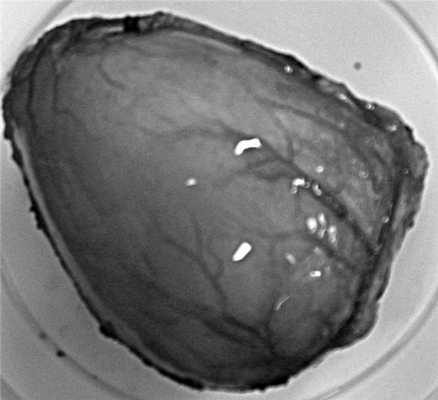

Макропрепарат размером 57×11×56 мм, по структуре напоминает желудок (рис. 3). Рисунок 3. Макропрепарат. Удаленный аномальный желудок. Содержимое - серозная жидкость соломенного цвета, оболочки выстланы эпителием.